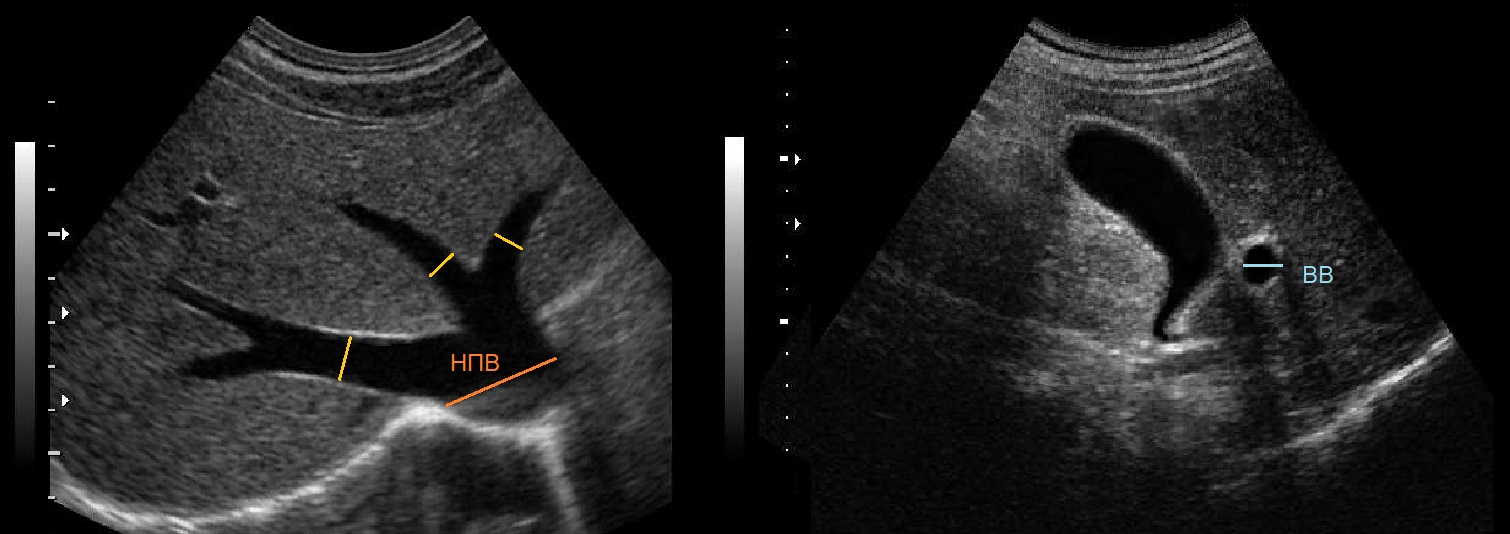

Как выглядит доля Риделя на УЗИ печени